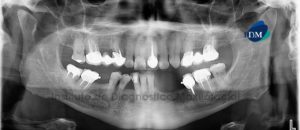

Paciente femenino, 37 años de edad, es referido al Instituto de Diagnóstico Maxilofacial (IDM) para evaluación general. A la evaluación de la radiografía panorámica se